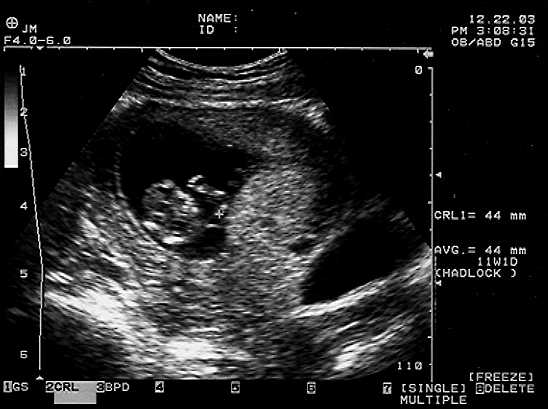

Baby A and Baby B pictures from the December 22 ultrasound are shown here at 11 weeks. Our next ultrasound is February 9, when an ultrasound technician (rather than the doctor) takes a detailed look at all the babies’ vital organs and makes sure they’re both on track. We’re so looking forward to seeing them again – but are ABSOLUTE about keeping their sexes a surprise!